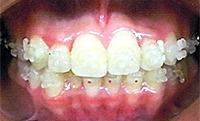

きさらぎ矯正歯科医院にて実際に矯正治療を行なった時の写真です。

乱ぐい歯(叢生)とは、歯が並ぶのに十分なスペースが確保できず、歯並びががたがたになってしまっていることをいいます。また、隙間が多く空いてしまっている状態を空隙歯列(すきっ歯)といいます。

いずれも、あごの大きさと歯の大きさのバランスが合わず、ところ狭しと色々な方向から歯が生えてきています。